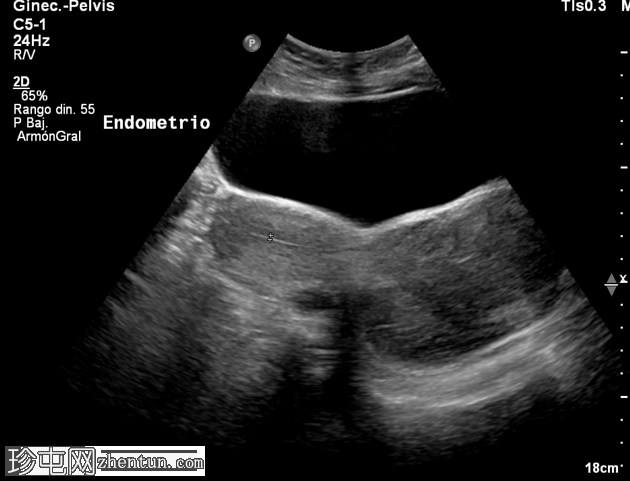

3.png

横切面

子宫前倾位。纵径、前后径、横径分别为145 × 41 × 58 mm。

由于存在一个边界清晰、形态不规则的低回声实性肿块,子宫呈异质性回声。该肿块位于宫颈区域,似乎延伸至阴道方向,大小为93 × 69 × 59 mm。

超声检查发现宫颈区域有一实性异质性肿块,延伸至阴道。鉴别诊断包括宫颈平滑肌瘤和宫颈肿瘤。需行盆腔MRI检查以明确病变性质。